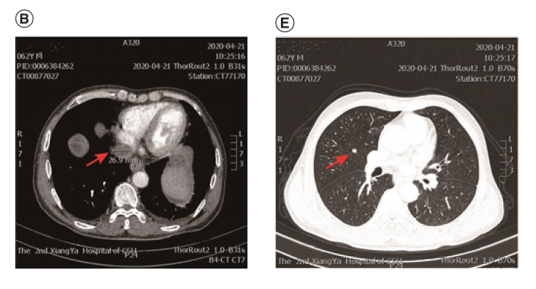

第三个疗程后约20天,腹部和胸部CT增强扫描显示IVC-RA连接处肿瘤血栓最大尺寸为26.9 mm,右肺上叶结节最大直径缩小至7mm。根据RECIST 1.1版疗效评价标准,肿瘤被确定为部分缓解(PR)。

在中断信迪利单抗和索拉非尼约一个月后,2020年6月3日的随访CT增强扫描显示,IVC-RA连接处肿瘤血栓(最大尺寸21.9 mm)和右上叶结节(最大直径6mm)继续缩小。